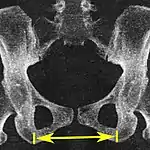

| Intertuberous diameter | ![]() |

The closest bony points of the ischial tuberosities | 10 to 12 cm.[6] | |